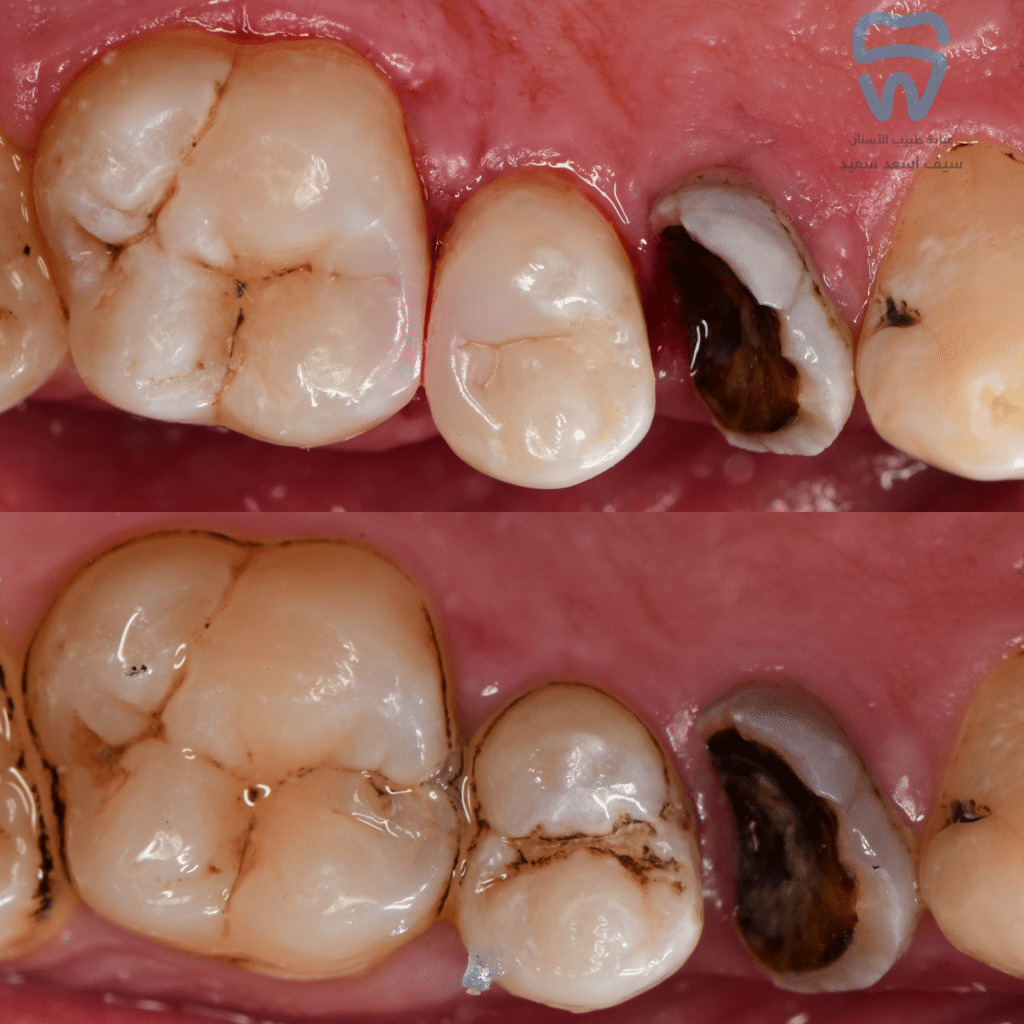

Initial situation

Caries excavation and cavity design

Buccal view of the cavities

Comparison of the contour before and after the procedure